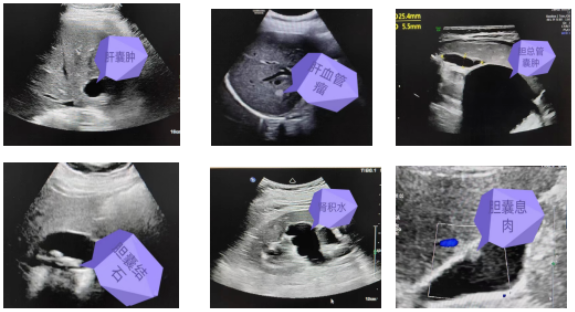

通過(guò)彩超檢查可以發(fā)現(xiàn)臟器的形態(tài)大小,有無(wú)占位性病變等。常見(jiàn)疾病如肝囊腫、肝血管瘤、膽總管囊腫、膽石癥、膽囊息肉、膽囊炎、肝臟脂肪變性、多脾癥、腎積水、腎結(jié)石、膀胱炎等。部分常見(jiàn)疾病超聲圖像如下: